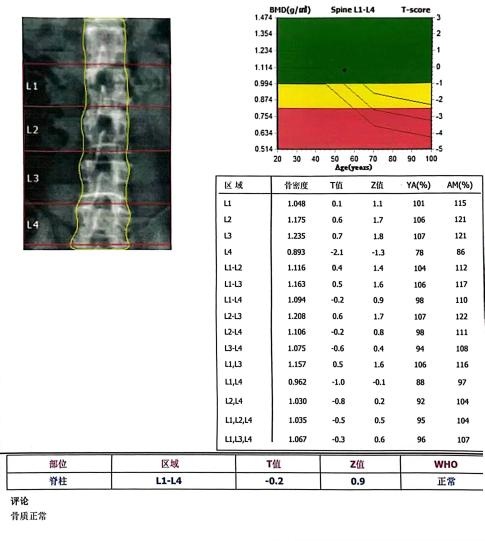

近日,我院影像科新引进一款美国GE Prodigy Pro 带enCORE v17软件的双能量X线骨密度仪。这台仪器是目前业内卓越创新型的系列产品,具备精确的骨密度测量功能,可用于骨质疏松的筛查、诊断、治疗监测及骨折风险预测,是一种无创、快速、安全的检查方法。除此之外,仪器还提供全面骨骼健康评估及高级体脂成分分析,可全面满足骨质疏松、肥胖及心血管疾病等各类人群的需要。

● 准确 患者在无需移动的前提下就可以找到准确的测试部位。精确掌握动态变化,为临床诊断、治疗提供客观、真实、可靠的依据。目前,双能 X 射线骨密度测量是世界卫生组织(WHO)诊断骨质疏松的“金标准”。

● 精准骨密度测量